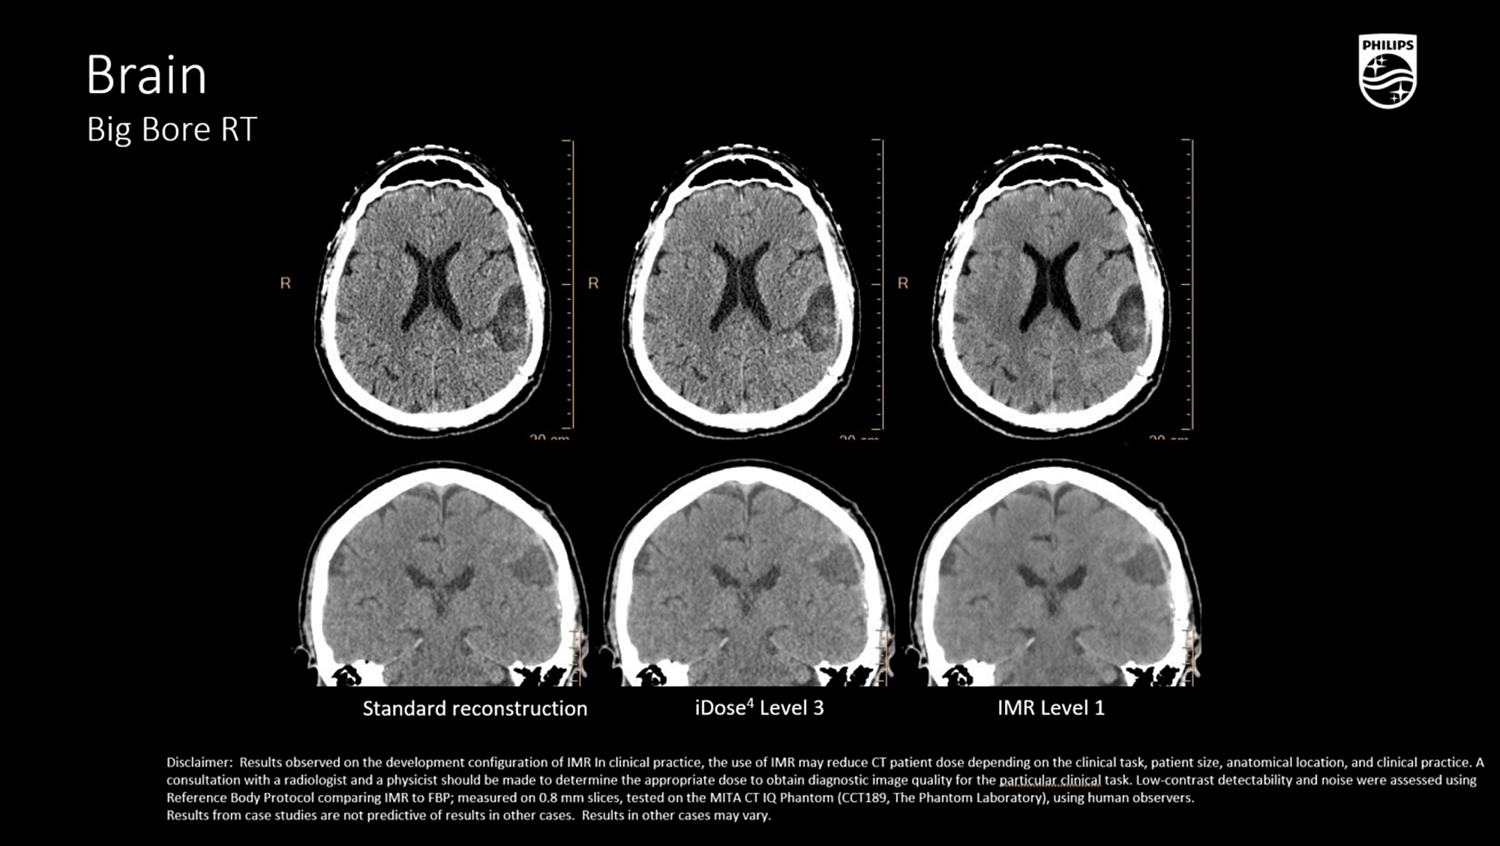

iDose⁴ (Iterative Dose Reduction Technology)

- Гибридная итеративная реконструкция в проекционном и изображен ческом пространстве повышает качество изображения и устраняет артефакты.

- Повышает контрастно-шумовое соотношение (CNR), снижая лучевую нагрузку на 50–80% при сохранении пространственного разрешения

- Поддержка низкокиловольтных протоколов (100/80 кВ), актуальна при планировании в педиатрии и у кахектических пациентов.